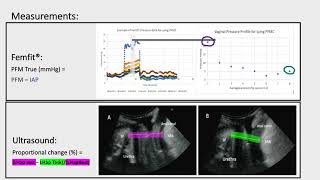

Female Pelvic floor Muscles #shorts #23421 Characterisation of the vaginal pressure profile (femfit) during exercise

Female Pelvic floor Muscles #shorts #23421 Characterisation of the vaginal pressure profile (femfit) during exercise